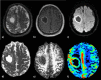

The role of conventional Magnetic Resonance Imaging (MRI) in the detection of cerebral tumors has been well established. However its excellent soft tissue visualization and variety of imaging sequences are in many cases non-specific for the assessment of brain tumor grading. Hence, advanced MRI techniques, like Diffusion-Weighted Imaging (DWI), Diffusion Tensor Imaging (DTI) and Dynamic-Susceptibility Contrast Imaging (DSCI), which are based on different contrast principles, have been used in the clinical routine to improve diagnostic accuracy. The variety of quantitative information derived from these techniques provides significant structural and functional information in a cellular level, highlighting aspects of the underlying brain pathophysiology. The present work, reviews physical principles and recent results obtained using DWI/DTI and DSCI, in tumor characterization and grading of the most common cerebral neoplasms, and discusses how the available MR quantitative data can be utilized through advanced methods of analysis, in order to optimize clinical decision making.